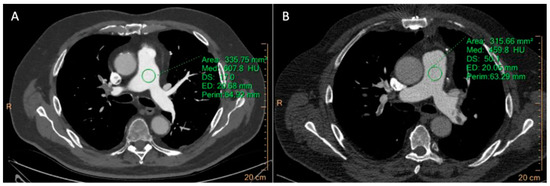

3.2.2. CTPA

| CTPA | MPA | 697.91 ± 10.76 | 334.87 ± 23.3 | <0.0001 | 62.14 ± 17.3 | 20.47 ± 13.5 | <0.0001 | 60.7 ± 19.45 | 10.77 ± 5.76 | <0.0001 |

| LPA | 644.61 ± 11.88 | 302.89 ± 19.45 | <0.0001 | 59.88 ± 18.2 | 19.5 ± 9.87 | <0.0001 | 57.43 ± 15.2 | 13.98 ± 6.32 | <0.0001 | |

| RPA | 651.43 ± 12.17 | 318.31 ± 26.84 | <0.0001 | 55.16 ± 16.1 | 22.54 ± 10.7 | <0.0001 | 54.6 ± 13.33 | 14.6 ± 8.69 | <0.0001 | |